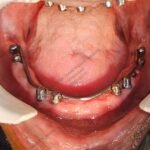

C1005 zygomatic basal implant full mouth – Ali Hasan 4

Dr. N.B. Singh